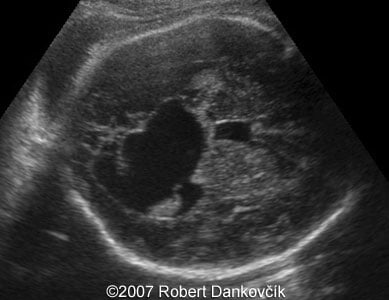

Images 5, 6: Color Doppler (image 5, left) and 2D sonogram showing two vessel umbilical cord.